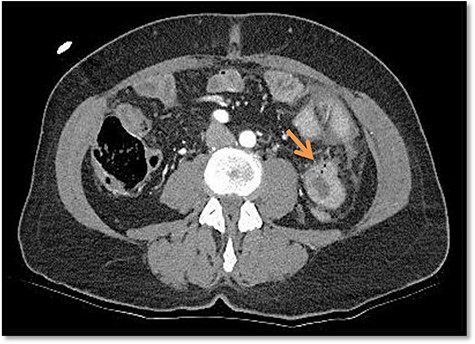

Due to the unclear sonography findings, a computed tomography (CT) scan was performed, which was concerning for a bowel perforation and traumatic hematoma of the jejunum in the left upper quadrant (Fig. 2). Also rib fractures of left costae VII, IX–XII were detected.

Considering the clinical presentation and the CT scan, we performed an emergency diagnostic laparoscopy. On the overview laparoscopy, we found free fluid in the left hemiabdomen as well as signs of moderate peritonitis (Fig. 3).